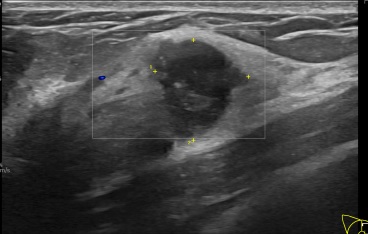

상기환자는  우측유방 만져지는 멍울로 내원하신 50대초반

여성분으로 의심스러운 우측혹 조직검사 시행해 유방암 진단되었습니다